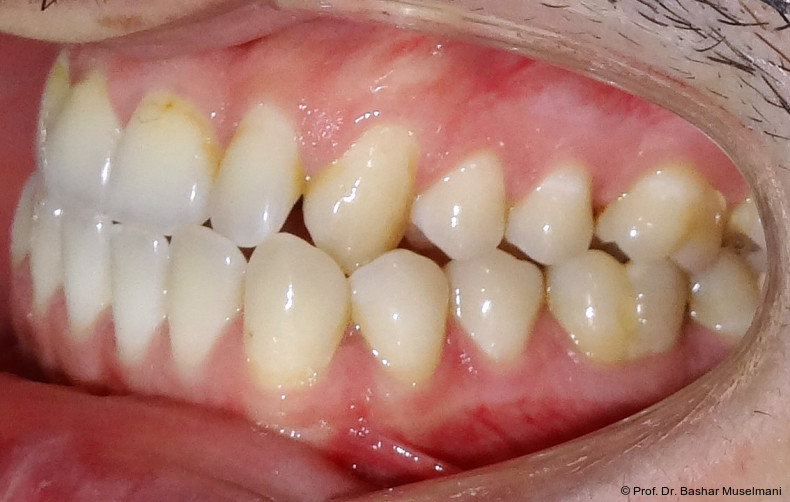

Der Patient (28 Jahre 8 Monate) stellte sich mit einer skelettalen Klasse III sowie einer Mittellinienabweichung nach links vor.

Klinische Befunde

• leicht konkaves Gesichts- und Mundprofil

• posterior positionierter Unterkiefer (VW)

• retroinkliniert stehende Unterkieferfront

Die Abbildungen 1 bis 3 zeigen die initiale klinische und radiologische Ausgangssituation.